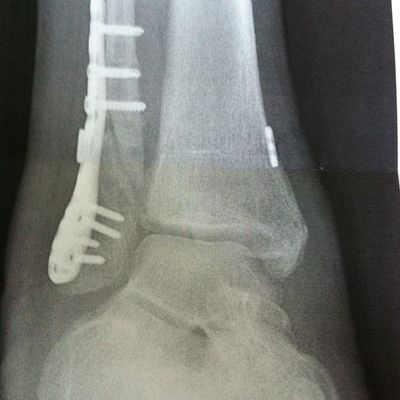

Fehlstelung verheilte Fibula Reoperation: 06.05.2011

Diagnose: in fehlstelung verheilte fibula und instabile malleolengabel 4 monate nach malleolar- luxationsfraktura rechts. operation: 06.05.2011 metallentfernug der fibula (platte=schrauben) mediale arthotomie zur narbenextraktion korrigierende (varisierende und verlängernde ) osteotomie des assenknöchels stabilisation mit winkelstabiler platte (